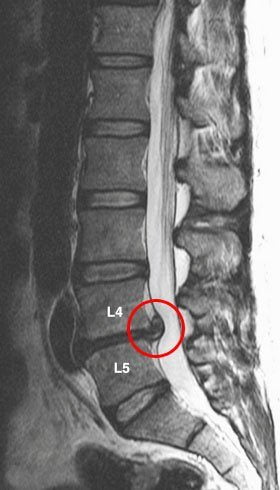

- Боль внизу спины справа. Такая локализация боли может свидетельствовать о патологии позвоночника и образовании межпозвонковых грыж. Еще одна возможная проблема – заболевания мочевыделительной системы. В последнем случае, какое бы положение больной не пытался занять, ничто не принесет ему облегчения и не ослабит боль.

Это самая распространенная группа заболеваний, которые приводят к развитию болевого синдрома в спине. Если долгое время болит спина справа, то необходимо думать о возможной патологии позвоночника.

Главным виновником боли в спине является остеохондроз. Локализация болезненных ощущений будет зависеть от того, какой участок позвоночника патологически изменен. Чаще всего страдает поясничный отдел позвоночника. При этом возникает постоянная ноющая боль внизу справа или слева. При поражении грудного отдела, болезненные ощущения могут локализироваться выше поясницы или под лопаткой.

При развитии осложнений остеохондроза (защемление нервов, их воспаление — радикулит) боль приобретает другой характер.

Развивается проецируемый болевой синдром – болезненные ощущения иррадиируют по ходу вовлеченных нервных окончаний (в руку, в ногу). Такая боль может иметь постоянный характер (люмбалгия, торакалгия) или в виде прострела (люмбого, торакаго).

Заболевания позвоночника

Ведущий симптом всех патологий позвоночника — боль в спине. Ее появление справа типично для одностороннего ущемления нервного корешка. Это часто происходит при остеохондрозе шейно-грудного, грудного, поясничного, пояснично-крестцового отделов позвоночника. Особенно часто боли возникают при его уже развившихся осложнениях: протрузии, межпозвоночной грыже, дискогенной миелопатии, корешковом синдроме.

Тянущая, постоянная ноющая боль в пояснице может быть спровоцирована воспалением органов малого таза. Но в подавляющем большинстве случаев она указывает на деструктивно-дегенеративные изменения в межпозвонковых дисках и позвонках. Острая боль в поясничном отделе характерна для воспаления нервного корешка или его сдавления, травмирования сформировавшейся межпозвоночной грыжей.